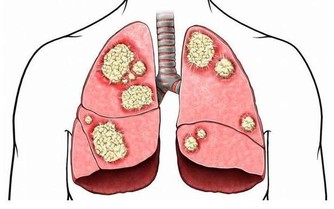

9、癌變、腫瘤化

細胞為了適應新的環境只有突變,癌細胞是在嚴重缺水,缺氧,缺營養的情況下形成,

從一個癌細胞發展到綠豆大小需要10-15年時間,

而從綠豆大小發展成雞蛋大小僅需要一年,癌症的潛伏期最少都有10-15年時間。